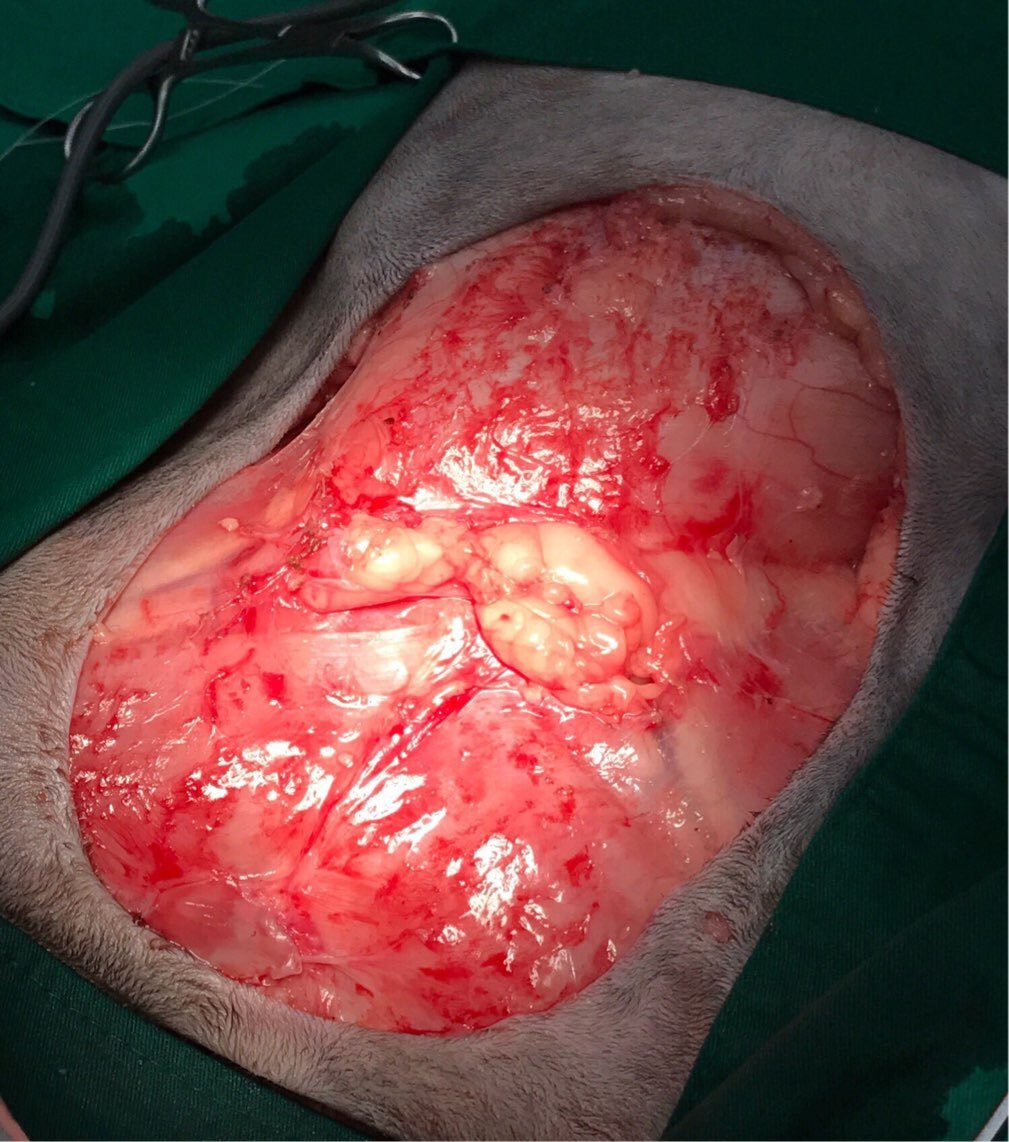

主題: 收受到撞擊導致皮下脂肪發炎,肚子大如水球的黑珍珠 申請者姓名: 吳怡萱 花色: 申請日期: 2017-10-03 16:52:15 申請者部落格: 申請者臉書網址: 所在縣市/合作醫院: 台北市/澄諾動物醫院 治療費用: 35460元 需求人數: 37人 已結案 (2024-06-01 13:22:23) 報名人員: Aisha Lung(已付款)、洪凱威(已付款)、Patrick x3(已付款)、mmgirls77(已付款)、silviacat(已付款)、菲力克斯(已付款)、Katze Chen(已付款)、Joe Hook(已付款)、Joyce Chen x2(已付款)、kuroneko(已付款)、Helen Yu(已付款)、邱凱偉(已付款)、邱凱偉、郭庭甄 x2(已付款)、Evan(已付款)、opel0209(已付款)、李坤財(已付款)、薇薇安(已付款)、Ting Huang x2(已付款)、山姆大叔(已付款)、ali(已付款)、Abby Lin(已付款)、Angelwang維(已付款)、Rebecca(已付款)、hideaki x3(已付款)、Flower Zhang(已付款)、House Hsu(已付款)、Yumiko Lee(已付款)、Betty Kao(已付款)、Autumn Tree(已付款)、Coffeemilk(已付款)、 候補人員: 動物病情說明: 平日餵養的浪貓媽媽黑珍珠

9/7進行腫塊摘除及皮下引流管放置

引發肚子增大的原因是皮下脂肪壞死發炎

研判是受到重大外力創傷造成⋯

而且術後傷口內發炎液體蠻多的

在使用類固醇注射後 發炎液體才慢慢減少

目前已經把手術放置傷口內引流管移除

結果醫生謹慎照了X光後發現

她的右側骨盆有裂傷⋯

還需要一段時間關籠修復